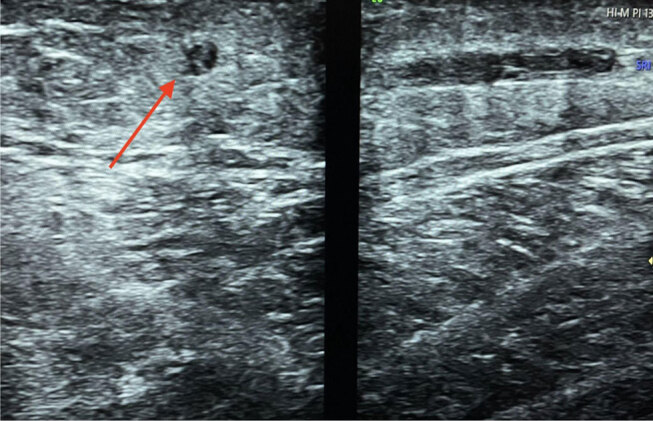

Abstract Image